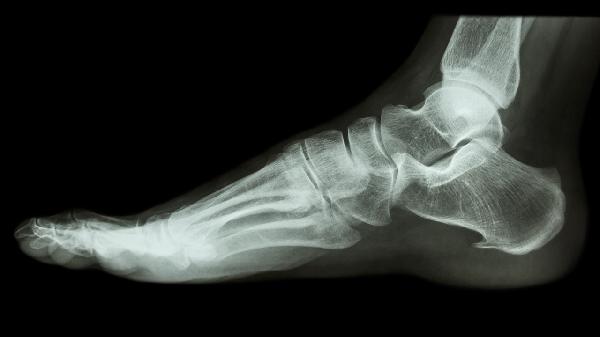

脚后跟骨刺如何治疗 介绍脚后跟骨刺的三个疗法

脚后跟骨刺可通过药物治疗、物理治疗、手术治疗三种方式缓解。脚后跟骨刺通常与足底筋膜慢性劳损、跟骨受力不均、退行性改变等因素有关。